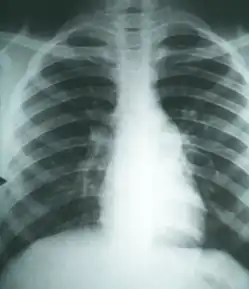

Imaging

Chest X-rays rarely demonstrate nodules or cavities in the lungs, but these images commonly demonstrate lung opacification, pleural effusions, or enlargement of lymph nodes associated with the lungs.[4] Computed tomography scans of the chest are more sensitive than chest X-rays to detect these changes.[4]